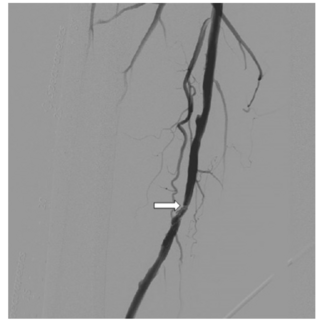

Alhazmi and colleagues describe a patient presenting with diminished distal flow in all 3 below-the-knee vessels, despite successful recanalization and patency of the upstream SFA, and absence of significant residual stenosis.